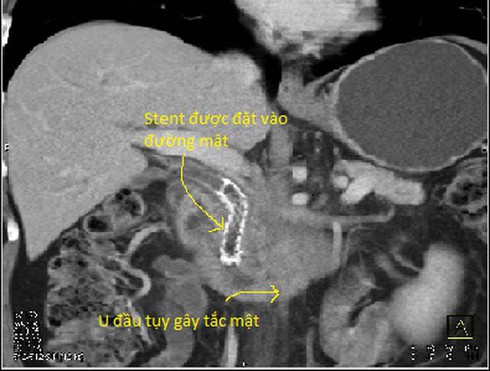

Trong các xét nghiệm để chẩn đoán ung thư tụy, chụp cắt lớp vi tính có vai trò quan trọng nhất. Qua đó, bác sĩ không những phát hiện khối u tụy mà còn đánh giá mức độ lan rộng khối u, tình trạng di căn hạch … Từ đó cũng giúp đánh giá khả năng phẫu thuật triệt căn cũng như khả năng can thiệp để giải quyết các biến chứng do u gây ra: tắc mật (đặt stent đường mật, dẫn lưu đường mật qua da), đau (phong bế đám rối thần kinh giảm đau)…